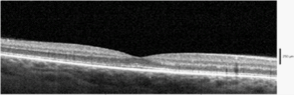

A 37-year-old woman (gravida 2, para 1, abortus 0), following an uncomplicated pregnancy except for a history of insulin-dependent gestational diabetes with good glycaemic control and a local Varicella-Zoster infection which treated successfully, underwent elective caesarean section under spinal anaesthesia with bupivacaine hydrochloride (10mg). Surgery was uneventful and two healthy twin-girls were delivered. Corticosteroids were at no point given. Antibiotics were given intraoperatively. Four days after the caesarean section the patient experienced a sudden decrease of visual acuity combined with a central scotoma and metamorphopsia in her right eye. At presentation, best-corrected visual acuity of the right eye was 8/20 with metamorphopsia, a central scotoma in Amsler's grid and blurred vision. Funduscopy of the right eye revealed a serous elevation of the macula (Figure 1 (A−C)). Fluorescein angiography (FA) disclosed three expanding points of fluorescein leakage at the foveolar avascular zone. Optical coherence tomography (OCT) sections through the macula showed a neurosensory retinal detachment with an increase in retinal thickness equal to 558μm.

Figure 1a RA: Fundus photograph of central serous chorioretinopathy in 37-year old woman 4 days after caesarean section. A serous detachment of the macula with subretinal fluid and RPE-bumps is seen. Visual acuity: 8/20.